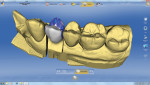

The introduction of monolithic lithium-disilicate and monolithic zirconia restorations brought an explosion of software development for full-contour design (Figure 16). Today, many companies sell software and/or milling equipment for designing full-contour restorations.

Implant abutment design for zirconia or titanium abutments has also benefited from full-contour software development. Once a full-contour restoration is designed for the edentulous space, the implant abutment can be designed within the full-contour crown, idealizing restorative thickness and support for the final implant-supported restoration (Figure 17). Easier-to-use software for full-contour design capability also benefits the design of zirconia restorations with strategic and minimal esthetic layering. By producing contours in the digital environment that closely approximate correct esthetics and utilizing more translucent zirconia, restorations can be created that are mostly monolithic zirconia and have only a thin bilayer of weaker layering ceramic applied to visible zones of the crown (eg, Diadem Precision Technology, diademprecision.com; and 3Shape).22,23

The author’s primary fabrication process for single posterior restorations is digital design and milling (eg, 3Shape, Diadem, Sirona inLab). For larger anterior cases, a matrix of the provisional restorations and wax injection is used to create waxed and pressed restorations from lithium disilicate. Two- and 3-unit anterior bridges are also made with waxed and pressed lithium disilicate. Posterior bridges can be fabricated from milled lithium disilicate fused to a zirconia substructure. The author still uses PFMs occasionally, and gold remains a great posterior restoration.